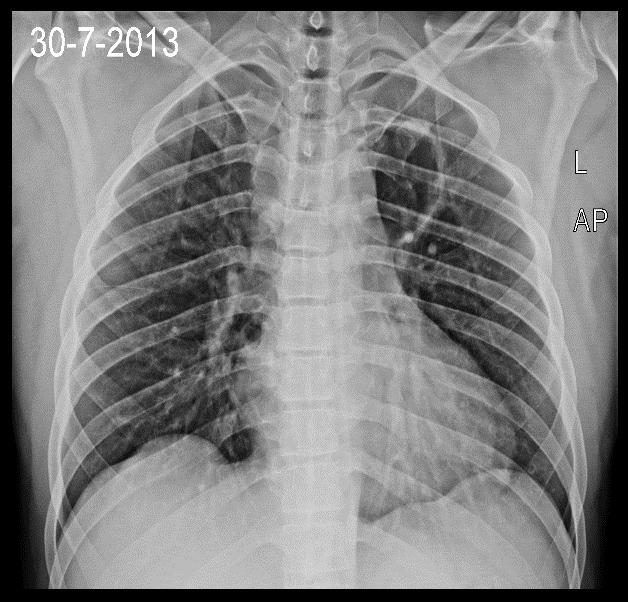

Bei der Suche nach der Ursache wurde auf einem

Röntgenbild der Lunge ein etwa 5 cm großer Hohlraum im linken oberen Lungenlappen

festgestellt, der am ehesten einem Lungenabszess entsprach. Das Blutbild war unauffällig, MRT des

Runder Hohlraum im linken oberen Lungenlappen.